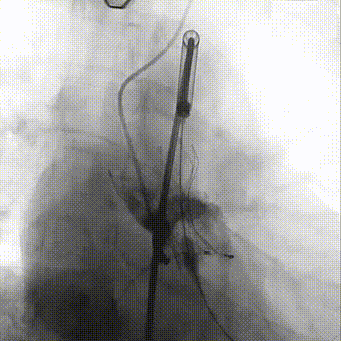

手术影像记录

主动脉根部造影

20mm TaurusAtlas球囊

输送系统过弓

确定初始释放位

瓣膜稳定释放至工作位

TaurusOne AV23mm瓣膜瓣下3-4mm 工作位造影

瓣膜完全释放

瓣膜位置理想

瓣膜植入前压差:121mmHg

瓣膜植入后即刻压差:16mmHg